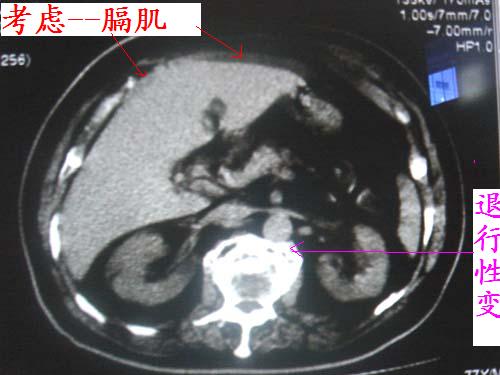

经各位老师一说,我还真拿不准了,最好连续层面观察就能鉴别是否是膈肌及容积效应所致。细节决定成败,期待高手帮忙解惑!!!不过本人还是支持正常表现的。

学习了!看了大家发言,总结一下战友的意见:

1有可能为 积液

2正常增厚肝包膜

3腹腔脂肪

4容积效应

5膈肌

6韧带附着点